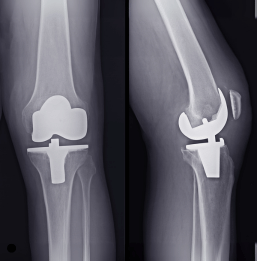

Knee & Hip Replacement

Expert in hip and knee replacement, restoring mobility and improving lives with advanced orthopedic care.

Knee Replacement

Knee replacement surgery reduces chronic pain, improves joint function, and restores strength for an active, confident lifestyle.